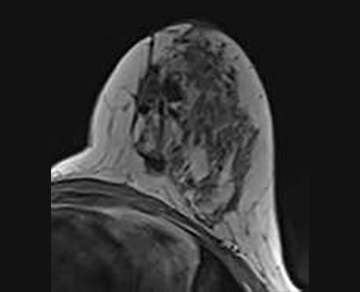

Architectural distortion at the lumpectomy site is an expected finding, and represents a benign (BI-RADS 2) post-surgical scar (Figure 1). Surgical clips will appear as foci of metallic susceptibility artifact.